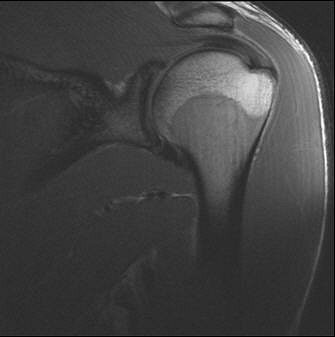

![]() |

| A case of turf toe. Above, right first MTP sagittal PD image. Middle, first MTP sagittal GRE. Below, first MTP sagittal STIR. |